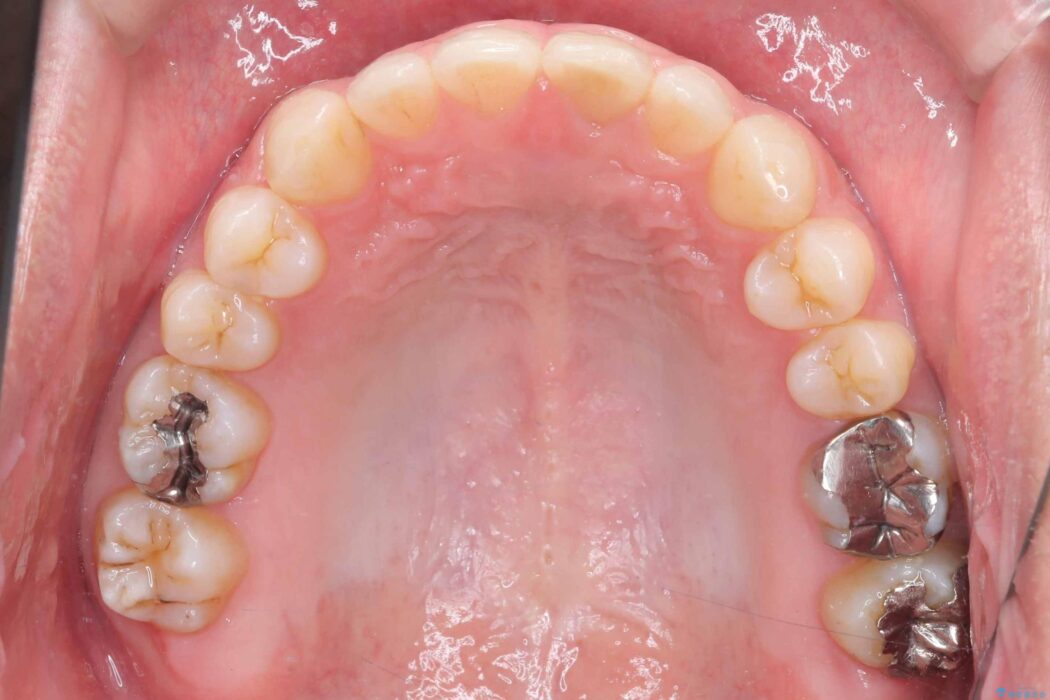

正中離開・叢生のほかに、上下の奥歯が全く咬み合わないシザーズバイトの状態も認められました。

歯の隙間とデコボコ、シザーズバイトも改善され、咬み合わせや見た目が整い、患者様にも大変ご満足いただけました。